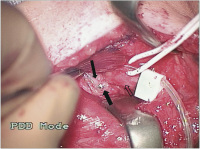

Intraoperativer Situs

Abbildung 1: Intraoperativer Situs. Eine neurale Struktur auf dem Gefäß-Nerven-Bündel kann fälschlicherweise als N. vagus interpretiert werden (dicker schwarzer Pfeil). Der N. vagus selbst ist nicht zu erkennen. Lateral ist die V. jugularis (schmaler schwarzer Pfeil), medial die A. carotis (umrandeter Pfeil).